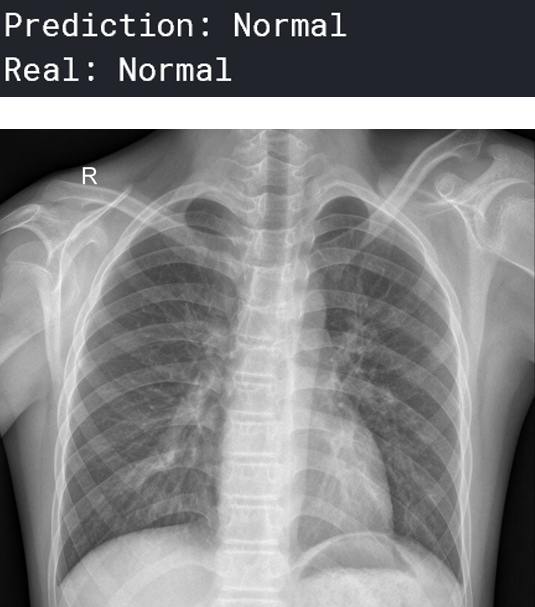

可视化预测

现在,我们可以可视化一些图像和预测。 预测“正常”的人:

一个预测为“肺炎”的人:

你可以想象这在医疗行业会有多大的帮助——人工智能可以在人类可能无法诊断肺炎的任务中提供很多帮助。